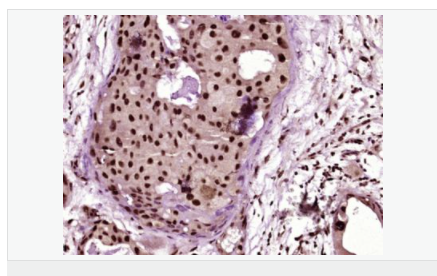

產(chǎn)品介紹The product of this gene phosphorylates the beta-2-adrenergic receptor and appears to mediate agonist-specific desensitization observed at high agonist concentrations. This protein is an ubiquitous cytosolic enzyme that specifically phosphorylates the activated form of the beta-adrenergic and related G-protein-coupled receptors. Abnormal coupling of beta-adrenergic receptor to G protein is involved in the pathogenesis of the failing heart. [provided by RefSeq].

Function:

Specifically phosphorylates the agonist-occupied form of the beta-adrenergic and closely related receptors, probably inducing a desensitization of them. Key regulator of LPAR1 signaling. Competes with RALA for binding to LPAR1 thus affecting the signaling properties of the receptor. Desensitizes LPAR1 and LPAR2 in a phosphorylation-independent manner.

Tissue Specificity:

Expressed in peripheral blood leukocytes.